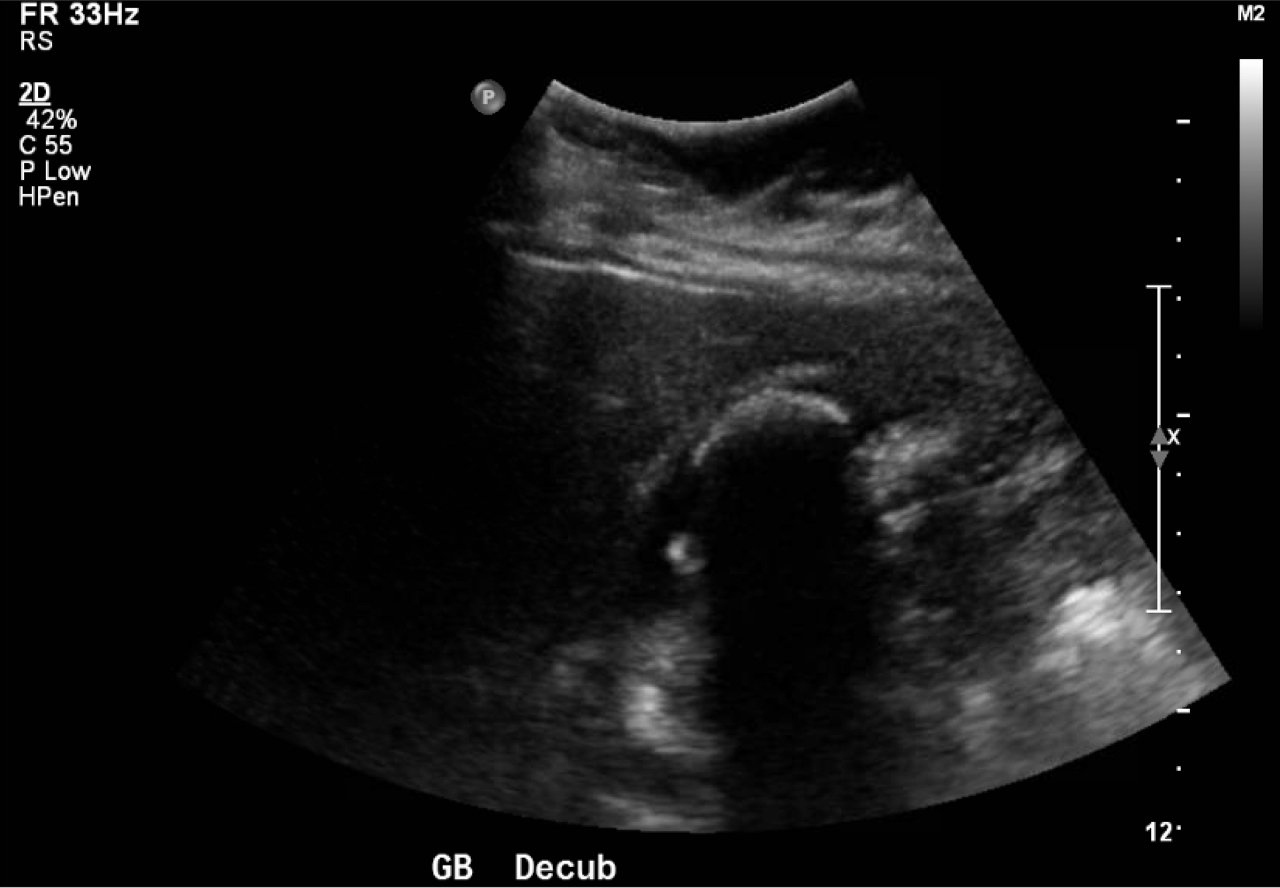

Abdominal ultrasound showed the classic presentation of the Wall-Echo-Shadow (WES) sign. The superficial aspect of the gallbladder wall is represented by a hyperechogenic curve. Below this, bile fluid is represented by hypoechogenicity. Underneath the bile fluid is the echo of the dense border created by the collection of gallstones, represented by a hyperechogenic curve. Due to the high density of the gallstones, nothing deeper can be visualized (including other gallstones or the far end of the gallbladder); this is the shadow.

The WES sign, first described in the early 1980s, is a clear way of identifying cholelithiasis when the condition has progressed to fill the entire lumen of the gallbladder.1 In this case, the lumen of the gallbladder looks hypoechogenic relative to the surrounding tissue, much like an empty gallbladder. This is due to the border of the dense stones opposing the near wall of the gallbladder casting a shadow over everything distal to the stones. These key visualization techniques decrease non-visualization of chronic cholelithiasis.2,3,4 In most cases, WES sign is sufficient to diagnose cholelithiasis. Of note, “porcelain gallbladder” or collapsed duodenum can have the potential produce similar ultrasonographic findings.4,5